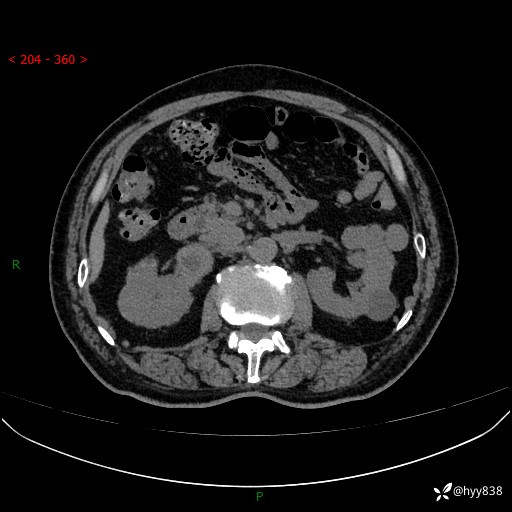

【患者信息】:76岁/男

【主诉】:检查发现右侧肾上腺占位6天

【现病史及既往史】:患者6天前体检发现右侧肾上腺占位,无腰痛,无放射痛,无尿频、尿急、尿痛及肉眼血尿,无畏寒、发热,无恶心、呕吐,今为求进一步治疗,遂来我院就诊,门诊拟“右侧肾上腺占位”收住入院。 起病以来,患者精神、饮食、睡眠可,大小便如常,体力体重无明显变化。

【检查】:肾上腺CT平扫+增强